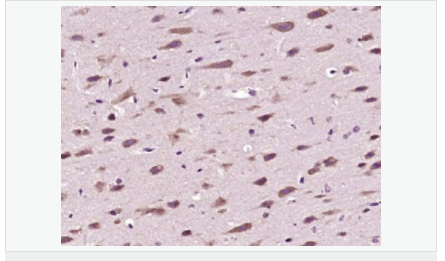

交叉反應(yīng):Human,Mouse,Rat(predicted:Pig,Cow,Horse,Rabbit) 推薦應(yīng)用:IHC-P,IHC-F,IF,ELISA

| 產(chǎn)品應(yīng)用 | ELISA=1:5000-10000 IHC-P=1:100-500 IHC-F=1:100-500 IF=1:100-500 (石蠟切片需做抗原修復(fù)) not yet tested in other applications. optimal dilutions/concentrations should be determined by the end user. |